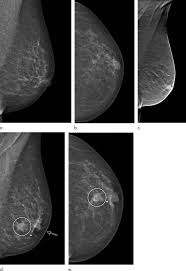

What Does Breast Cancer Look Like On Mammogram Images / Focal Asymmetric Densities Seen At Mammography Us And Pathologic Correlation Radiographics : A screening mammogram is performed at regular intervals to check for breast cancer in women who have no signs or symptoms of the disease.. What does breast cancer look like on a mammogram? The feel of a breast lump depends on its cause, location, and growth. Not all women have calcifications in their breasts—but most do. These deposits show up as tiny white spots on a mammogram, and there may be only one or two, or too many to count, says jay baker, md, a breast imaging specialist at the duke cancer center.most people assume that what doctors are looking for on a mammogram are lumps, dr. The calcifications associated with breast cancer are usually quite small, often described as microcalcifications.

Look at your old studies, if available. Any area that does not look like normal tissue is a possible cause for concern. However, a mammogram is not perfect and it is difficult to detect abnormalities in a person with dense breasts. We'll show you breast cancer pictures to help you identify any physical traits of the condition. Screening mammograms have been used since the 1980s. Not all women have calcifications in their breasts—but most do. The 3d mammogram images can be analyzed as a whole or examined in small fractions for greater detail. A diagnostic mammogram is used to check for breast cancer when there is a sign or symptom of disease.

Calcifications usually can't be felt, but they appear on a mammogram. If microcalcifications are found on your mammogram, the radiologist will do the following to help determine what if anything needs to be done: It's common to have dense breasts. Palpation of benign breast masses. Generally, whiter mammogram images indicate denser breasts. According to the american cancer society (acs), the most common sign of breast cancer is a new lump or mass in the breast. Specialist doctors (radiologists) trained to interpret mammograms can identify any abnormal areas, masses or calcium. Look at your old studies, if available. Breast mri images are combined, using a computer, to create detailed pictures. To determine whether that lump is benign, your doctor will likely order a mammogram and breast ultrasound. What does breast cancer look like on a mammogram? We'll show you breast cancer pictures to help you identify any physical traits of the condition. The skin of the breast might also appear puckered, like the skin of an orange.

So, an ultrasound is typically a 'second look' type of application. Not all women have calcifications in their breasts—but most do. The 3d mammogram images can be analyzed as a whole or examined in small fractions for greater detail. The doctor reading your mammogram will be looking for different types of breast changes, such as small white spots called calcifications, larger abnormal areas called masses, and other suspicious areas that could be signs of cancer. Look at your old studies, if available.